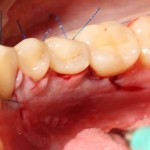

Теперь запиливаем «костную дверцу» на ее законное место:

И накладываем швы.

Благодаря сделанному нами разрезу, мы можем вывести узелки на внешнюю сторону альвеолярного отростка, что будет удобнее и комфортнее для пациента: